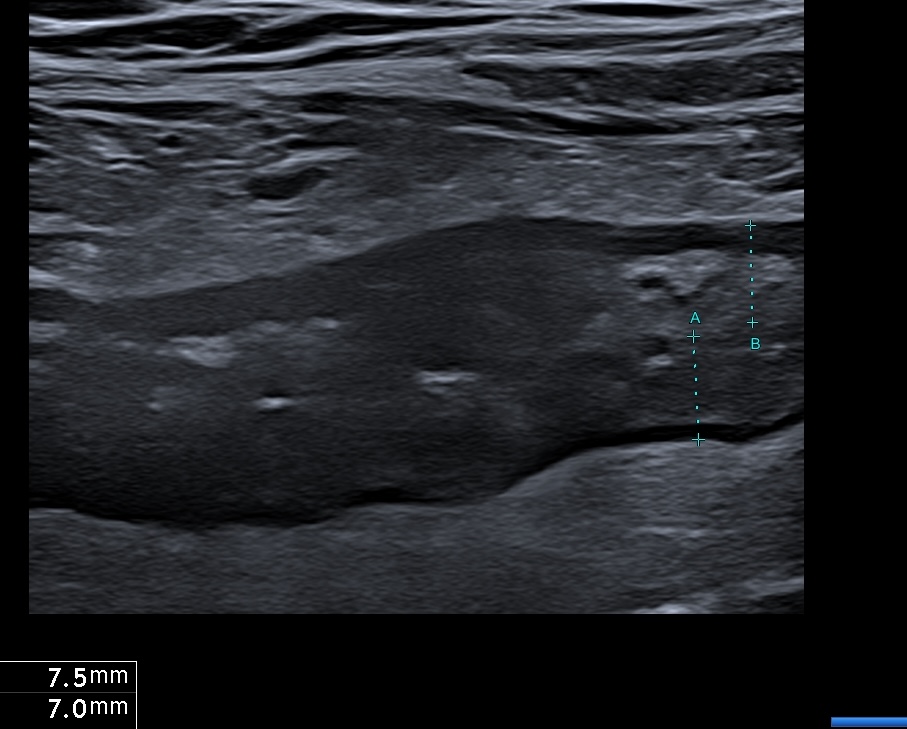

- On la mesure mieux sur une coupe transversale.

Coupe transversale permet de mieux aprécier l'inflammation de la graisse